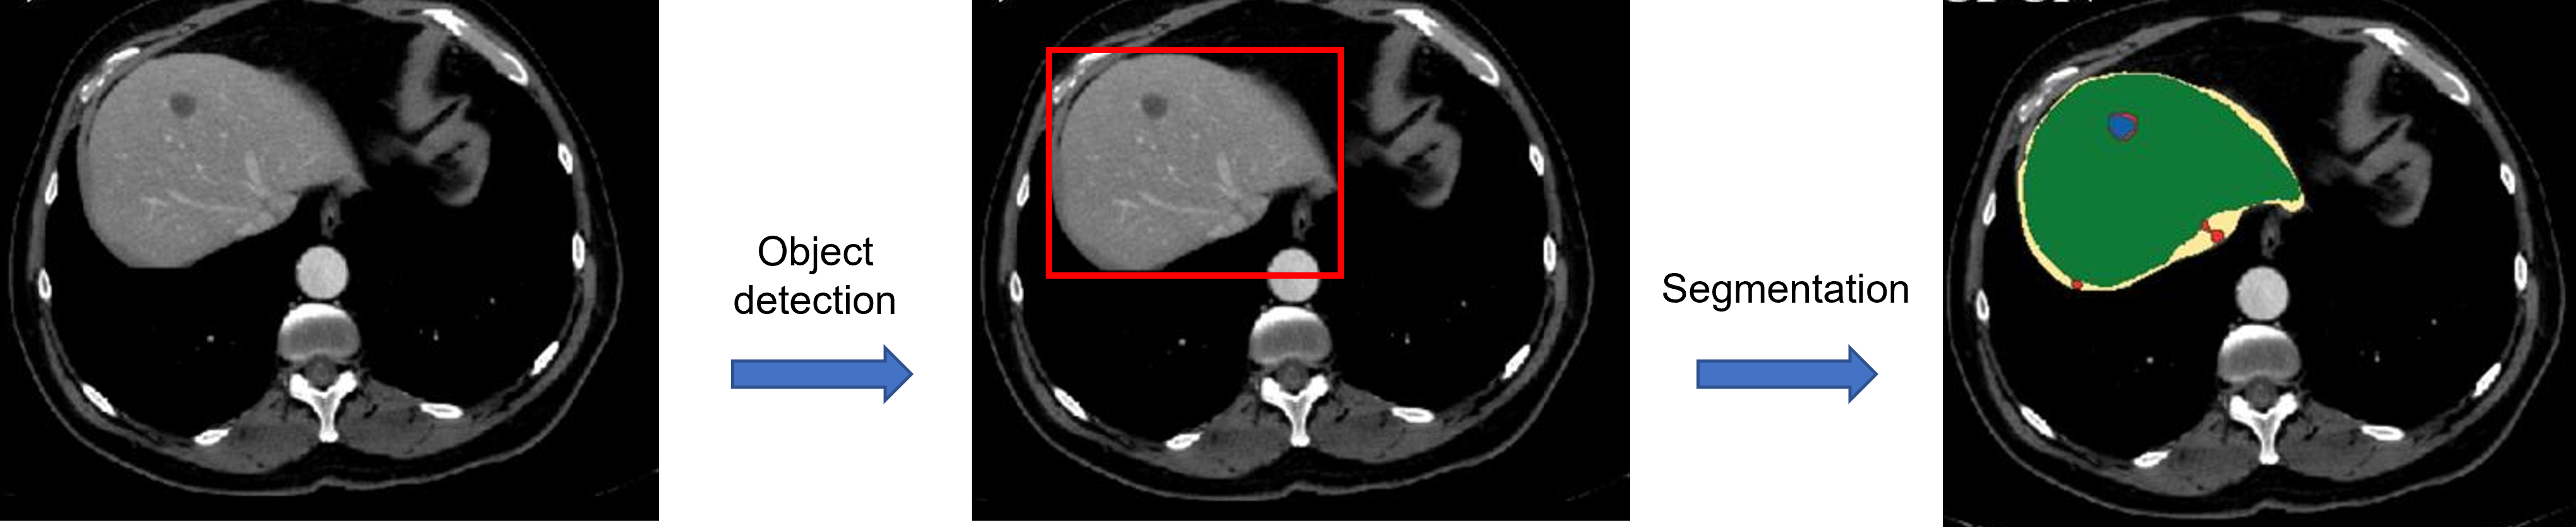

- 두 번째로 "end-to-end"가 아닌 모델은 cascade 방식의 모델입니다.

- 먼저, Segmentation 작업을 cascade 방식으로 진행할 수 있습니다.

- Segmentation 작업을 진행할 때, 우선 관심 영역을 detection 하고 (RoI detection), 해당 RoI 영역을 segmentation 하도록 설계할 수 있습니다.

- 즉, object detection 모델과, segmenation 모델을 각각 독립적으로 사용하는 것이죠.